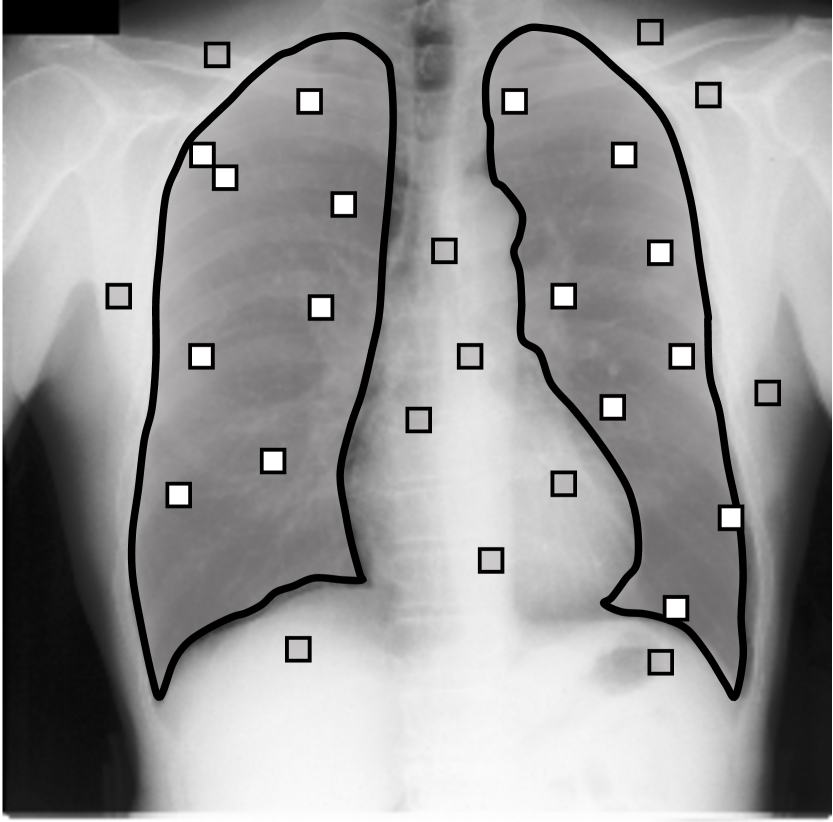

Real-world label noise. To evaluate with real-world label noise is challenging. We are not aware of any public medical image segmentation dataset that has both true labels and noisy labels from human annotators. Therefore, we use a multi-annotator dataset, LIDC-IDRI dataset (Armato III et al., 2015; Armato et al., 2011; Clark et al., 2013), and the coarse segmentation in a vision dataset, Cityscapes (Cordts et al., 2016). The LIDC-IDRI dataset consists of 1018 3D thorax CT scans where four radiologists have annotated multiple lung nodules in each scan. The dataset was annotated by 12 radiologists, and it is not possible to match an annotation to an expert. We use the majority voting as the true labels and the union of four annotations as noisy labels. We process and split the data exactly the same way as Kohl et al. (2018). Cityscapes dataset contains 5000 finely annotated images along with a coarse segmentation by human annotators that we use as the “noisy label”. We only focus on the ‘car’ class because (1) cars are popular objects and are frequently included in images; (2) the coarse annotation of cars is very similar to noisy annotation in medical imaging – they are reasonable distortions of the clean label without changing the topology. See Figure 4(c) for an example. The detailed settings of LIDC-IDRI and Cityscapes can be found in Appendix A.2.1.

Table 1 shows the segmentation results of different methods with synthetic noisy label settings on JSRT , ISIC 2017 and Brats 2020 dataset. Note that QAM cannot be applied to Brats 2020 dataset because their network is designed for 2D only. We compare DICE score (DSC) on testing sets (against the clean labels). For each setting, we train 5 different models, and report the mean DSC and standard deviation. In and , where biases show up in noisy labels, the proposed method outperforms the baselines by a big leap in total case. The compared methods, however, only work when little bias is included, like . is equivalent to setting in our Markov model, resulting in . We also test the proposed method on real-world label noise, results shows in Table 2. Figure 5 shows examples of label correction results. We provide more qualitative results in the Appendix A.4.